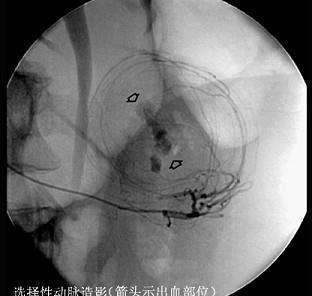

选项 A、大便隐血试验 B、纤维胃镜检查 C、胃液分析 D、胃肠道钡餐检查 E、选择性动脉造影

答案 B